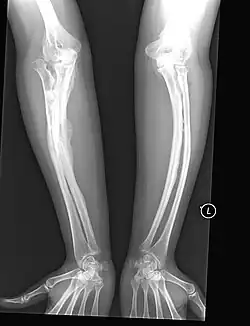

The main symptom of osteogenesis imperfecta is fragile, low mineral density bones; all types of OI have some bone involvement.[5] In moderate and especially severe OI, the long bones may be bowed, sometimes extremely so.[28] The weakness of the bones causes them to fracture easily—a study at the Endocrine Unit at the National Institute of Child Health in Karachi, Pakistan found an average of 5.8 fractures per year in untreated children.[29] Fractures typically occur much less after puberty, but begin to increase again in women after menopause and in men between the ages of 60 and 80.[1]: 486

Diagnosis is typically based on medical imaging, including plain X-rays, and symptoms. In severe OI, signs on medical imaging include abnormalities in all extremities and the spine.[97] As X-rays are often insensitive to the comparatively smaller bone density loss associated with type I OI, DEXA scans may be needed.[5]: 1514